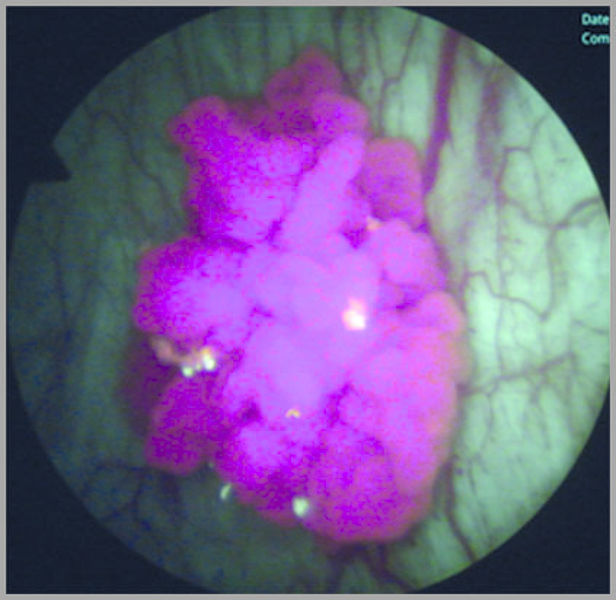

光动力学诊断是一种用于非肌层浸润性膀胱癌 (NMIBC) 早期诊断的腔内泌尿外科手术技术,多年来一直广泛应用,旨在减少 NMIBC 的进展和复发风险。

Richard Wolf 德国狼牌充分考虑了每一个细节,正在开发一种精确的光动力学诊断 (PDD) 系统 — System Blue蓝荧光内窥镜系统,为使用 Hexvix® 诊断膀胱癌创建一个全新的基准。系统组件与感光剂间呈理想协调状态,可显著改善肿瘤荧光,从而提高检出率。

通过比较氙吸收光谱技术与 ENDOLIGHT LED blue,发现 ENDOLIGHT LED blue LED 光源的发射带与 Hexvix® (PPIX) 的主要吸收带间呈理想协调状态。因此,可产生一种更强的肿瘤荧光。